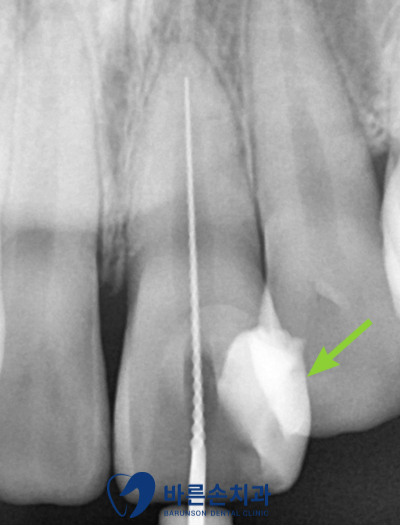

화살표 보시면 하얀색으로 되어있는 부분 보이시나요??

충치를 제거하고 레진이라는 재료로 치아 벽을 만들어준 모습입니다.

그 후에 안에 있는 신경을 바늘 같은 도구를 사용하여 제거해 줍니다.